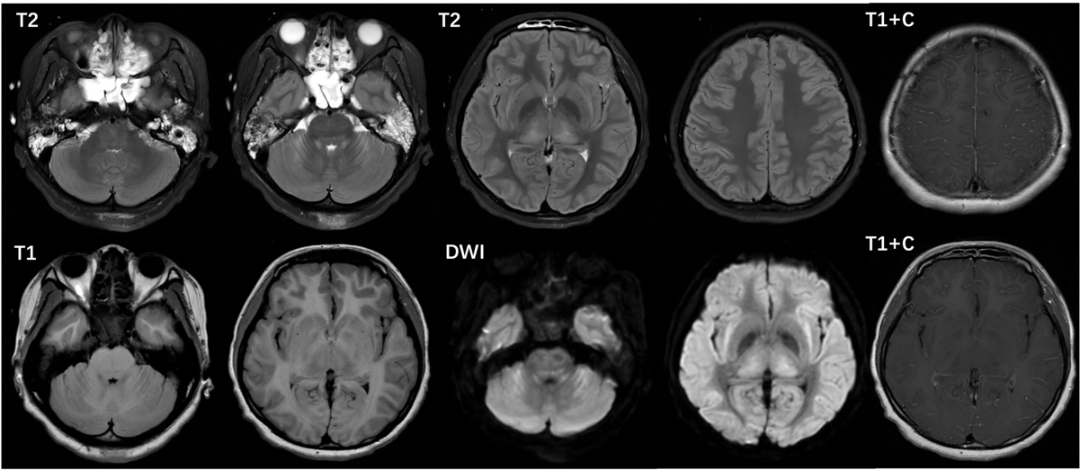

头颅CT:脑组织肿胀加重,部分脑沟裂池变浅、消失,丘脑可疑低密度影(2025年11月25日,图1)。

图1 头颅CT示脑组织肿胀(2025年11月20日);头颅CT示脑组织肿胀加重,部分脑沟裂池变浅、消失,丘脑可疑低密度影(2025年11月25日)。

头颅增强MRI+SWI:脑干、双侧小脑、丘脑和屏状核异常信号,软脑膜强化(图2)。

图2 头颅强MRI+SWI:脑干、双侧小脑、丘脑和屏状核异常信号,软脑膜强化(2025年11月25日)。